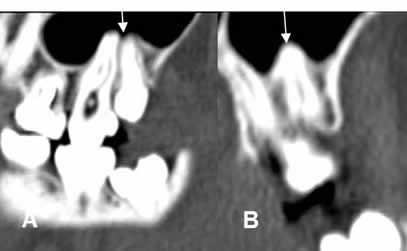

Fig 50. Periodontitis apical crónica.

A: TAC axial, B: TAC reconstrucción coronal y C: TAC reconstrucción sagital. Dilatación del espacio periapical, con la punta de la raíz en el centro de la lesión, por quiste radicular.